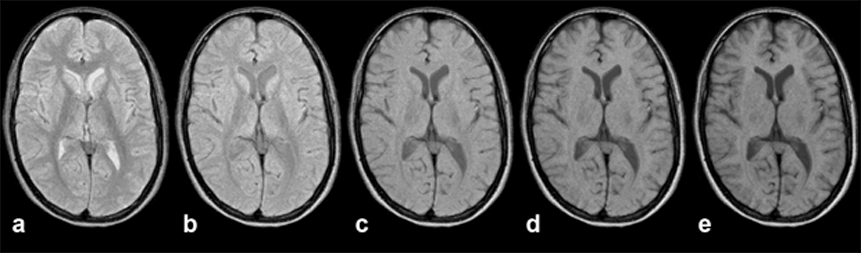

Figures 10-12 and 10-13 depict the typical signal intensity behavior of a GRE se­quen­ce, in this case a spoiled FLASH sequence. Commonly, the signal in­­ten­­si­­ties reach a maximum between 30° and 60°.

As we have seen with the signal in­ten­si­ty and contrast behavior of SE sequences, best contrast is not necessarily ob­tai­ned at the point of highest signal intensity. This is also the case in GRE se­que­nces, as the con­trast be­ha­vior of the brain images of Figure 10-13 shows. At the greatest signal in­ten­si­ty, there is poor or no contrast.

It turns out that images acquired using the Ernst angle tend to have rather poor con­trast. Higher flip angles have to be used to improve the contrast. The effect of this is a reduction of the signal left along the z-axis after the RF pulse. Thus, the sig­nal level depends on the rate at which the si­gnal recovered during TR; it is strong­ly T1-dependent. The image series in Figures 10-12 and 10-13 give an over­view of how contrast changes with in­­crea­s­ing flip angle.

Figura 10-12:

Gradient echo sequence (spoiled GRE). TR = 400 ms; TE = 20 ms. B₀ = 1.5 T. Because of the three va­ri­ables avail­able, there are nearly unlimited possibilities for changing ima­ge contrast. Generally, at low flip angles proton density dominates contrast, at high flip angles T1 becomes more important.

Images (through the brain of a normal volunteer): (a) α = 15°; (b) α = 30°; (c) α = 45°; (d) α = 60°; (e) α = 75°

Simulation software: MR Image Expert®